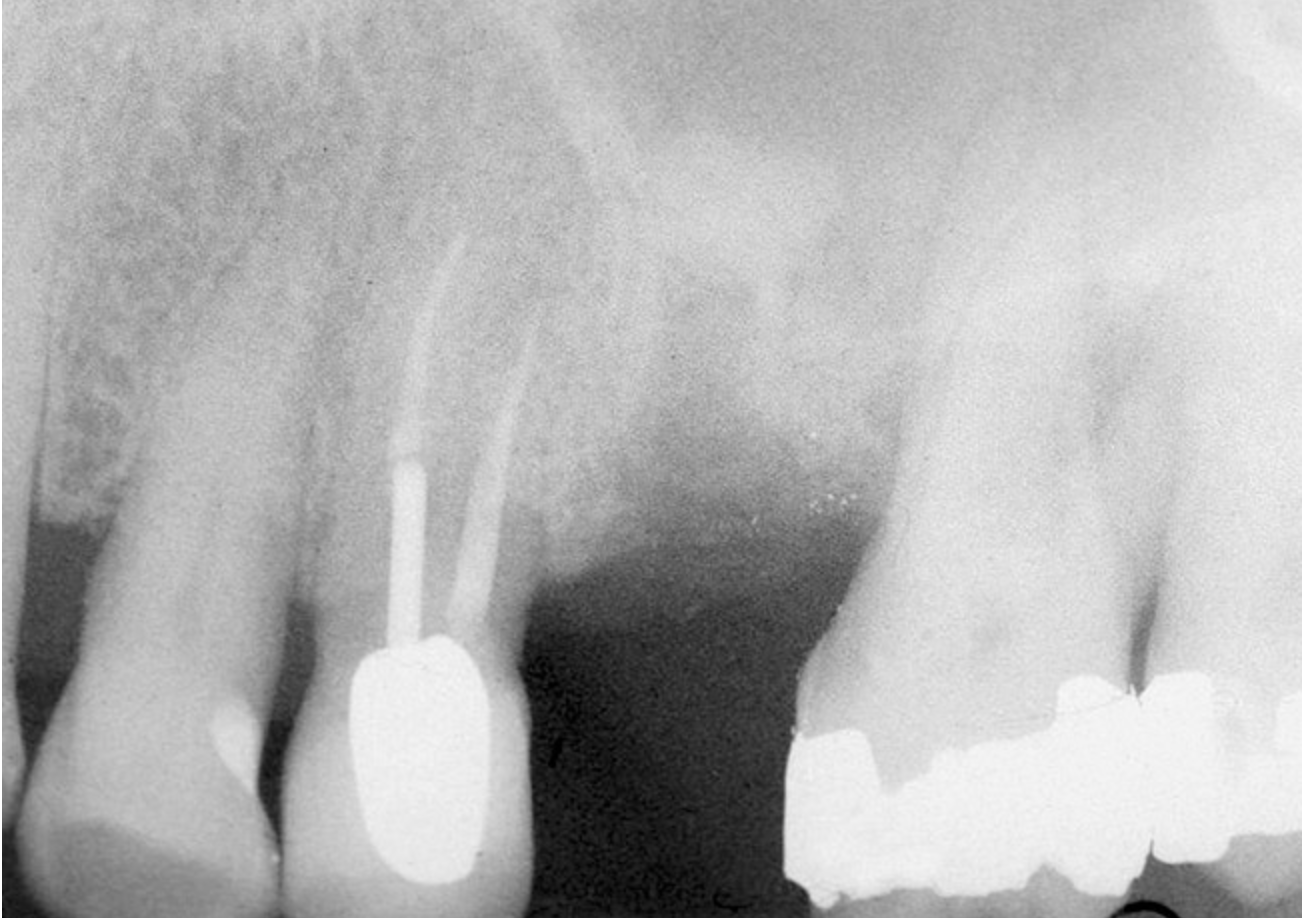

The 2-mm twist drill is used to create an osteotomy 1 mm short of the subantral floor. If any resistance is detected prior to reaching the 3-mm depth, drill penetration must be stopped, because the subantral cortical bone has possibly been reached. Any uncontrolled "push" would penetrate the bone and likely perforate the sinus membrane. A guide pin is then inserted and a radiograph taken to determine if drill penetration has terminated within 1 mm of the subantral floor (Figure 2). If the radiograph indicates that more than 1 mm of bone is present subantrally, the twist drill is used again to penetrate within 1 mm of the sinus floor. Alternately, an osteotomy tip for a piezosurgery unit can be used for this purpose. The final depth of penetration should be verified with another periapical film.

Figure 2  After drilling to a depth of 3 mm with a 2.1-mm twist drill, the guide pin was placed and a radiograph was taken to ascertain if the drill stopped within 1 mm of the subantral floor.

Figure 2

Figure 3  The osteotomy was completed with the 2.1-, 2.8-, and 3.5-mm twist drills without penetrating into the sinus.

Figure 3

Figure 4  After infracturing the subantral wall with a 3.5-mm osteotome, bone was added and the presence of a dome was confirmed with a radiograph.

Figure 4